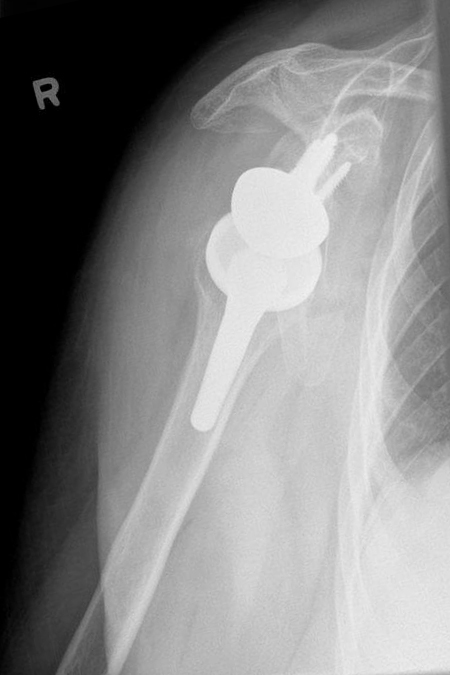

Primäre Omarthrose einer 84-jährigen Patientin auf der rechten Seite mit einem sich im 3D-CT darstellenden B2 Glenoid nach Walsh. Versorgung nach präoperativer virtueller Planung mit einer zementfreien Inversen Prothese. Alltagstaugliches Ergebnis mit Wiedergewinnung der Eigenständigkeit insbesondere auch in der Pflege ihrer eigenen Haare.

78-jährige Frau mit deutlicher Arthrose des Schultergelenks bei intakter Rotatorenmanschette – in der CT-Untersuchung keine wesentliche Dezentrierung des Gelenkes. Es wurde eine anatomische Schulterprothese mit kurzem Schaft Mitte 2019 eingesetzt mit gutem Ergebnis und Alltagstauglichkeit.

Deutliche Arthrose des Schultergelenkes mit intakter Sehnenführung. Einsetzen einer Kurzschaftendoprothese 2020 und nachfolgende Rehabilitation über 3 Monate. Sehr alltagstaugliches Ergebnis ohne Schmerzen.